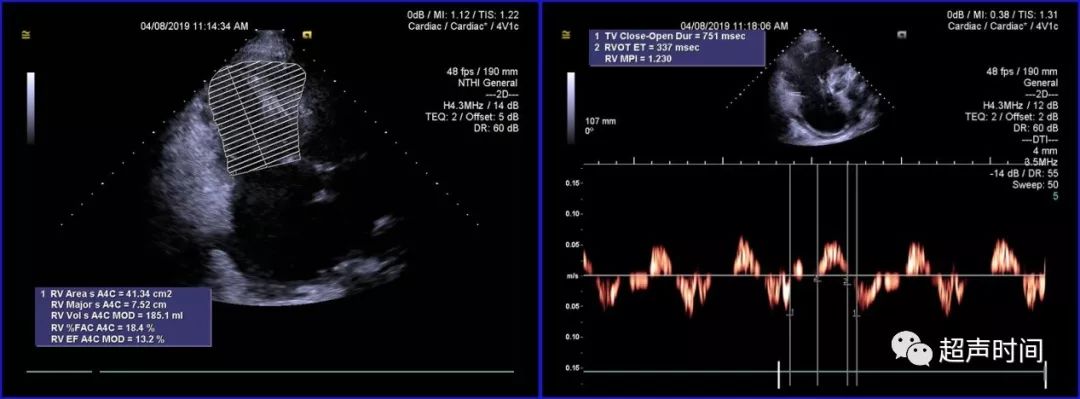

实用干货丨右心扩大的超声诊断分析

右位心的超声模板

镜面右位心的超声模板

超声心动

超声心动图